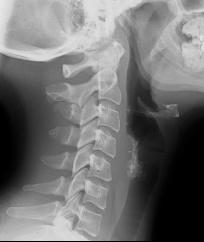

This is a lateral radiograph of the neck, which is sometimes done prior to other more definitive studies to look at the airway.

In Image A from our patient, the hyoid bone is shown in orange, and a very thick and inflamed epiglottis in red. The region of the valleculae is shown in green. This is an emergency, as epiglottitis can lead to complete airway obstruction. Image B is a comparison study to show the normal appearance of the epiglottis.